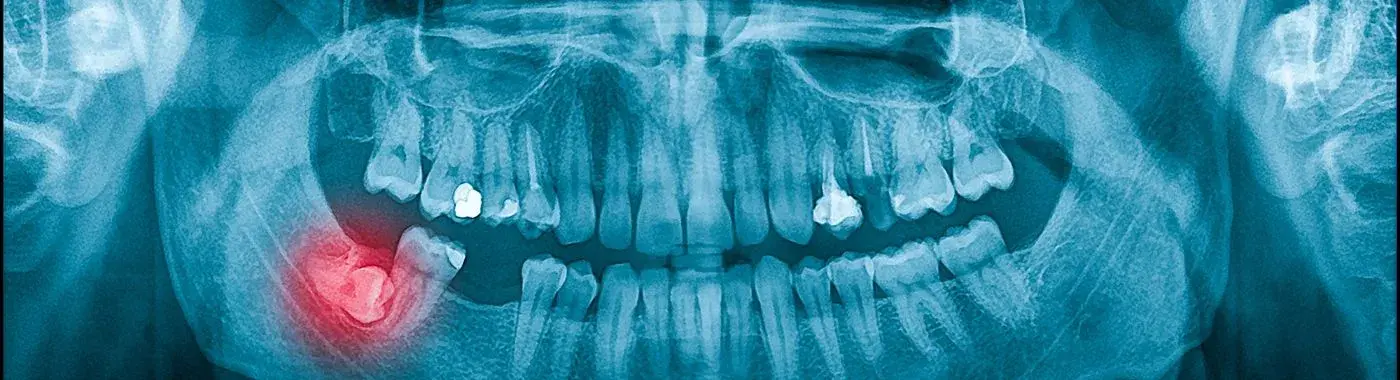

• X-rays: Dental X-rays are crucial for visualizing the position of the impacted tooth and assessing its relationship with surrounding teeth and structures.

• Cone Beam Computed Tomography (CBCT): In some cases, a 3D imaging technique may be used for a more detailed view of the impacted tooth and its surroundings.